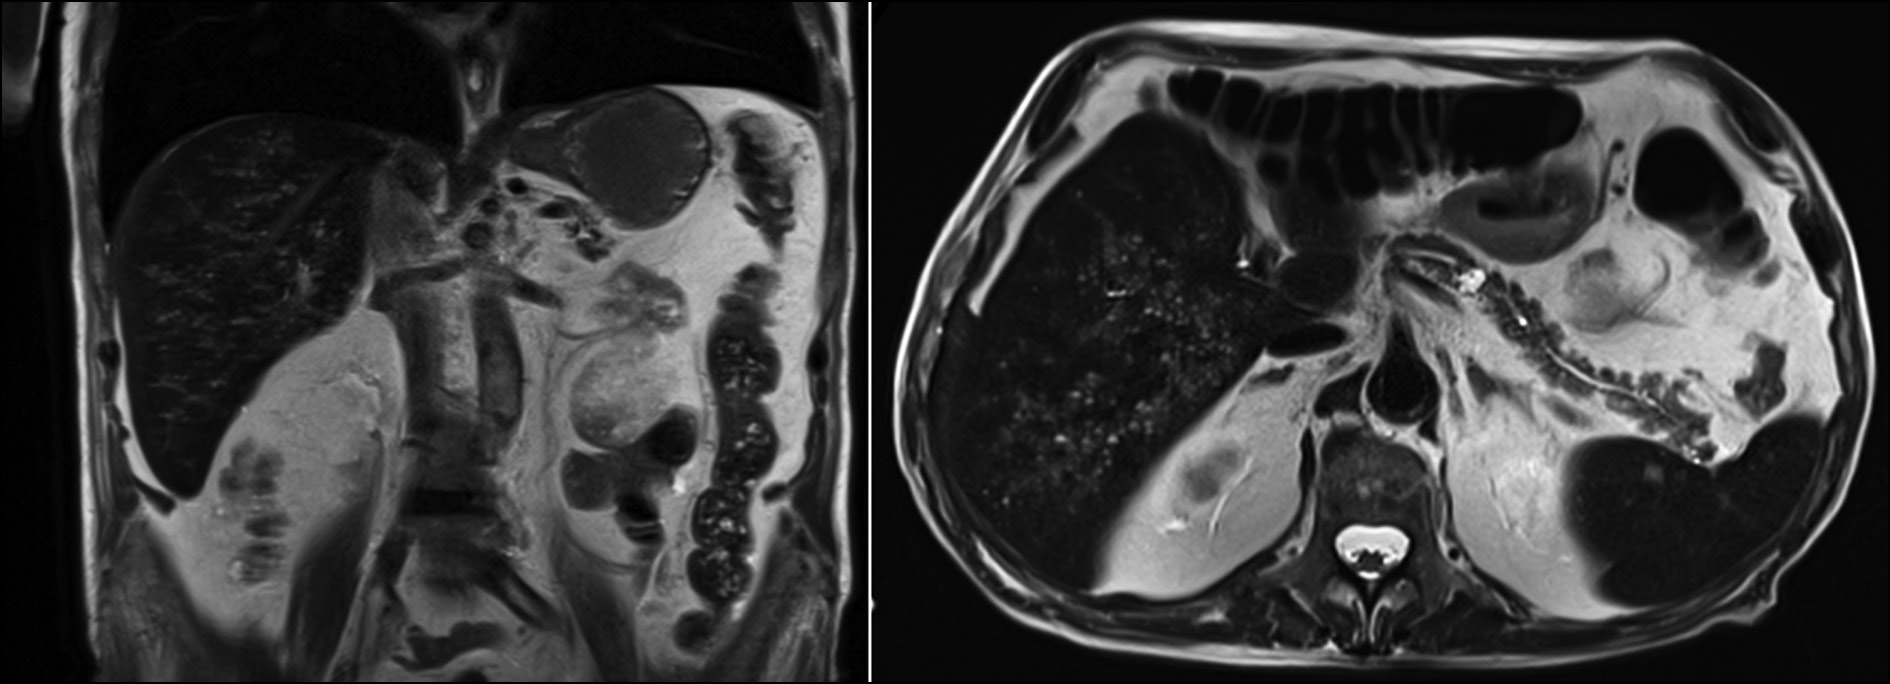

Subsequent MRI examination identified the same lesions with different characteristics in various sequences. In T2-weighted MRI images, the areas appear homogeneously and intensely hyperintense (Fig. 2).

Fig. 2. Coronal and axial MRI images with HASTE T2 sequence: multiple small hyperintense lesions throughout the hepatic area.